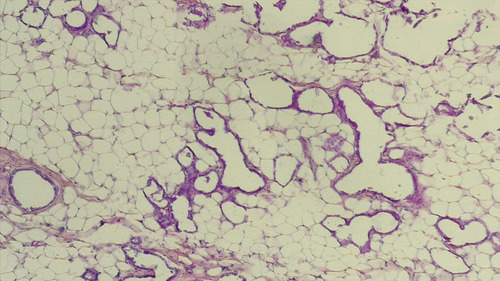

• tkanka podskórna

-tkanka występująca pod skórą, zbudowana z tkanki tłuszczowej żółtej i tkanki włóknistej luźnej

-jej grubość zależy od stanu odżywienia człowieka, wieku, płci, okolicy ciała

-zawiera dolne odcinki korzeni włosów, części wydzielnicze gruczołów potowych i niektóre receptory